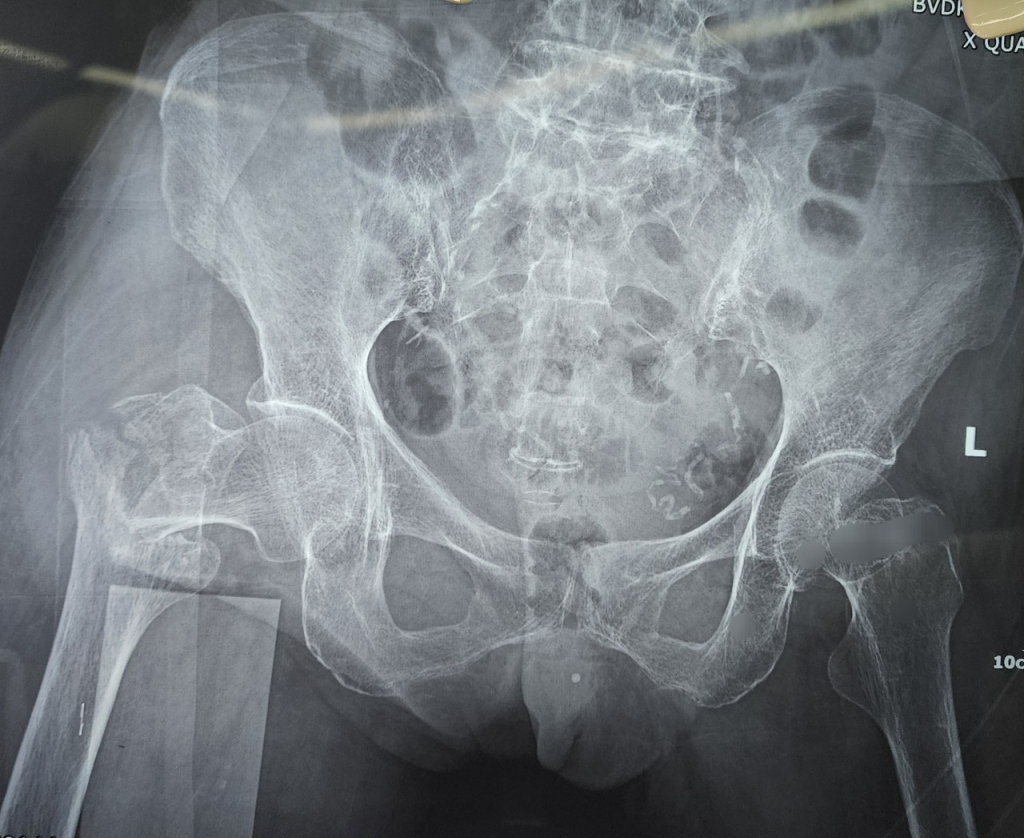

Bệnh viện đa khoa Vĩnh Đức vừa tiếp nhận trường hợp bệnh nhân nữ (81 tuổi, quê Quảng Ngãi) bị gãy liên mẫu chuyển xương đùi sau khi trượt ngã tại nhà. Với tiền sử tăng huyết áp, đái tháo đường và bệnh lý thiếu máu cơ tim Bệnh Viện Đa khoa Vĩnh Đức điều trị thường quy bằng phương pháp phẫu thuật hiện đại không mở ổ gãy sử dụng đinh PFNA dưới màng hình tăng sáng. Người nhà nhanh chóng thuê xe đưa bệnh nhân từ Quảng Ngãi ra Quảng Nam để được điều trị. Sau 2h di chuyển, 1h để làm các xét nghiệm cần thiết, Bệnh nhân đã được tiến hành hội chẩn chuyên môn toàn viện để đánh giá mức độ an toàn của ca phẫu thuật và đưa ra phương án điều trị hiệu quả nhất. Dưới sự phối hợp liên chuyên khoa gồm Khoa Ngoại Chấn thương chỉnh hình; Khoa Tim mạch và Khoa gây mê hồi sức, ngay trong ngày bệnh nhân được tiến hành phẫu thuật kết hợp xương bằng kỹ thuật xâm lấn tối thiểu, sử dụng đinh nội tủy đầu trên xương đùi thế hệ mới (PFNA). Thời gian phẫu thuật chưa đến 30 phút, ngay sau phẫu thuật 4h bệnh nhân có thể cử động chân gãy, sau 1 ngày có thể ngồi dậy và sau 2 ngày tập phục hồi chức năng đi lại dưới hỗ trợ khung tập đi . Bệnh nhân được xuất viện trở về Quảng ngãi sau 5 ngày nằm viện với niềm vui và phấn khởi của bệnh nhân và gia đình.

Gãy liên mấu chuyển xương đùi là loại gãy xương thường gặp, chiếm khoảng 55% trong các loại gãy xương ở đầu trên xương đùi. Bệnh có thể gặp ở mọi lứa tuổi nhưng hay gặp nhất là ở những người lớn tuổi (trên 60 tuổi), gặp ở nữ giới nhiều gấp 2 – 3 lần nam giới. Nguyên nhân chủ yếu do tai nạn sinh hoạt: ngã ở nhà vệ sinh, leo ghế thắp hương, thay quần, tai nạn giao thông… Khi bị gãy liên mấu chuyển xương đùi bệnh nhân không đứng dậy được, vận động háng rất đau, chân gãy ngắn hơn chân lành, bàn chân đổ xoay ngoài. Tỉ lệ tử vong lên tới 20 – 30% trong năm đầu sau chấn thương. Đa số bệnh nhân gãy liên mấu chuyển thường là người lớn tuổi, nhiều bệnh lý nội khoa kèm theo như tăng huyết áp, đái tháo đường, thiếu máu cơ tim làm cho khả năng phẫu thuật trở nên khó khăn và nguy hiểm với các phương pháp phẫu thuật mở . Tuy nhiên nếu không được phẫu thuật bệnh nhân sẽ tàn phế, nằm bất động lâu dài dẫn đến các biến chứng loét nhiễm trùng vùng da cùng cụt, viêm phổi, tắc mạch… và dẫn đến tử vong trong thời gian ngắn. Do đó Phương pháp phẫu thuật kết hợp xương là một trong những phương pháp điều trị xương đùi mang lại hiệu quả cao.